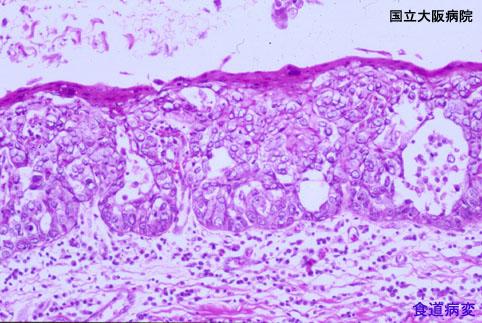

진행암과 동시성으로 발견된 표재형의 식도 유기저세포암 (증례제시:국립 오사카병원)

악성 상피성종양/류기저세포암

식도/하

마이크로

0형(표재형)/기타

40이상

mm